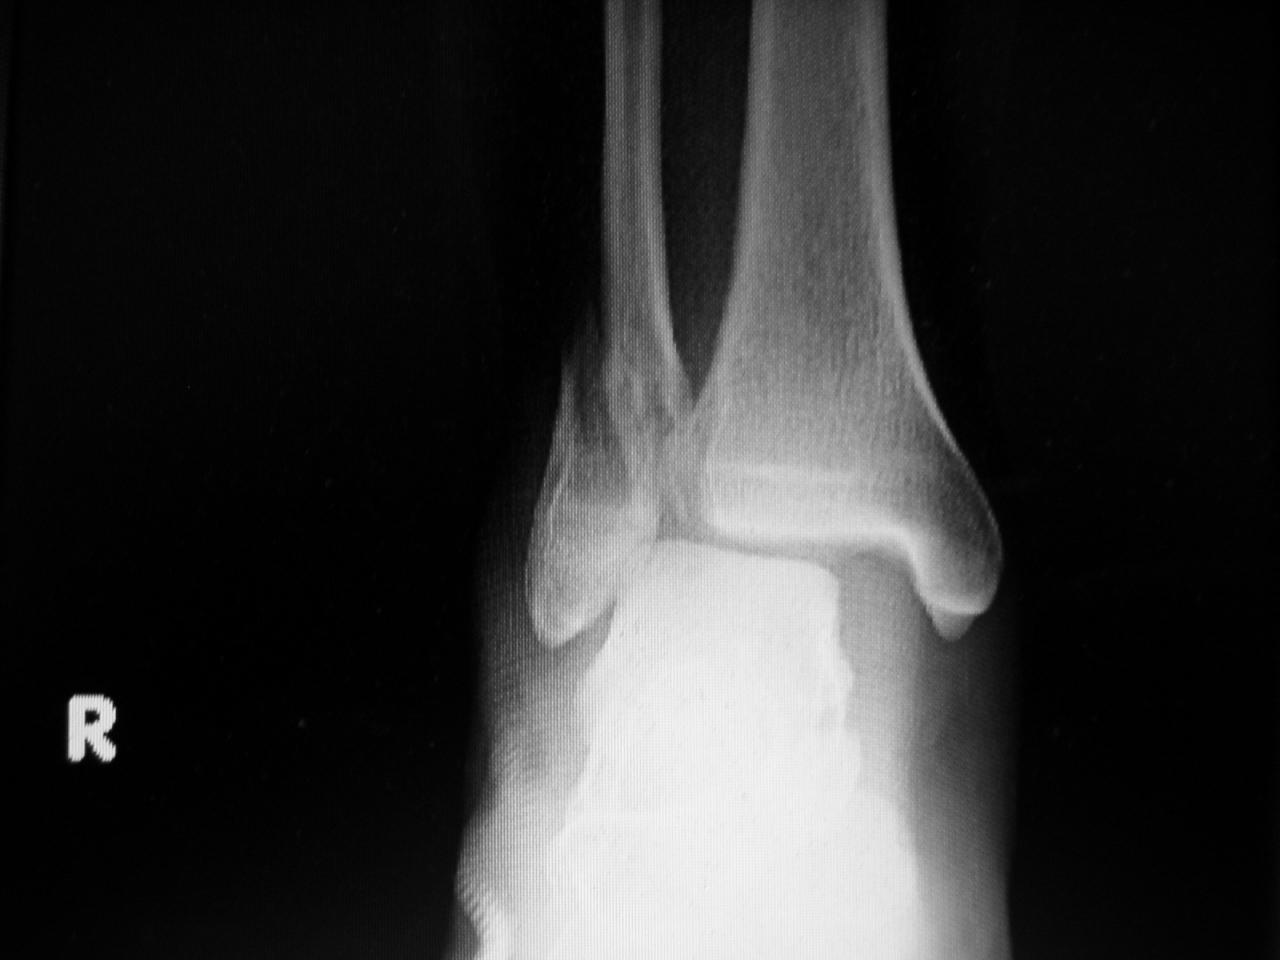

ちょっとしたアクシデントで足首の関節がバラバラに。<br />骨折は5度目だが、今回と4度目との間隔が開いてるので不安に。<br /><br />どちらにしても久し振りの入院、長期療養に突入だ!<br /><br /><br />レントゲン撮影の時は何時も「男前に撮ってくれぃ」と技師に言うのだが大抵は無視される。<br /><br /><br />そんなワケで治療は現在進行中であるのだ。

ちょっとしたアクシデントで足首の関節がバラバラに。

骨折は5度目だが、今回と4度目との間隔が開いてるので不安に。

レントゲン撮影の時は何時も「男前に撮ってくれぃ」と技師に言うのだが大抵は無視される。

でも、MRI画像よりレントゲン写真のほうがリアリティが。

暖かみもあるし。